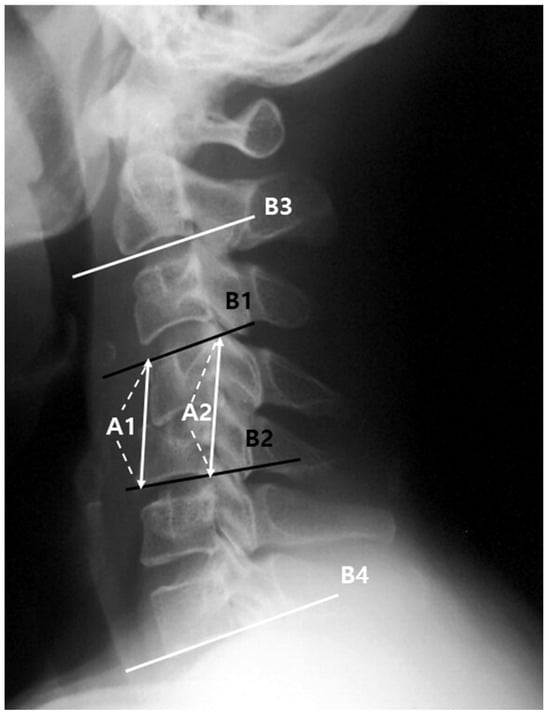

| Segmental angle (°) | |||||

| -First visit | −2.7 ± 3.1 | −2.4 ± 5.9 | −2.7 ± 4.7 | 1.000 * | (−1.2, 1.5) |

| -Last follow-up | −3.1 ± 3.8 | 2.7 ± 5.4 | −2.8 ± 4.6 | <0.001 * | (2.8, 9.2) |

| C2-C7 angle (°) | |||||

| -First visit | 8.4 ± 8.1 | 8.2 ± 7.8 | 9.4 ± 6.0 | 0.797 * | (−2.1, 2.5) |

| -Last follow-up | 8.1 ± 6.8 | 16.7 ± 8.4 | 9.1 ± 7.3 | 0.001 * | (3.2, 13.8) |

| Mean height change (%) | −19.3 ± 11.9 | 14.0 ± 15.8 | −7.8 ± 10.9 | <0.001 * | (18.5, 42.3) |